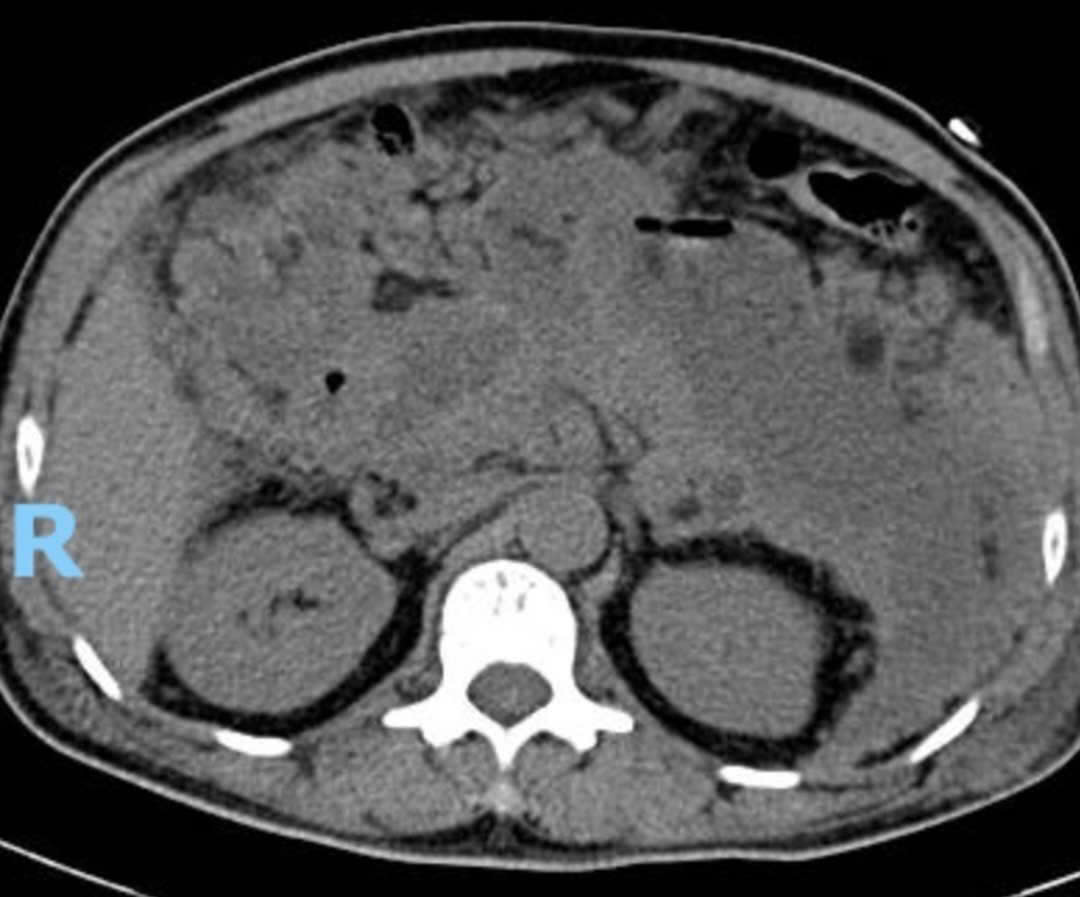

Hình ảnh cắt lớp vi tính của bệnh nhân trước dẫn lưu.

Tại đây, các bác sĩ tiến hành đặt ống nội khí quản thở máy, thay huyết tương, lọc máu liên tục. Ngoài ra, kết quả chụp cắt lớp vi tính ổ bụng lần 2 phát hiện bệnh nhân bị viêm tụy hoại tử với khối tụ dịch và tổ chức hoại tử lớn 11x8 cm ở thân, đuôi tụy.